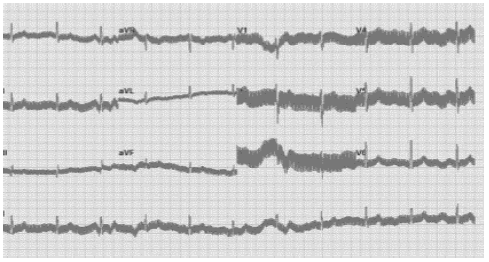

O equipamento de eletrocardiografia é responsável por registrar as variações na atividade

elétrica do coração. Nesse equipamento, dependendo do número de eletrodos, é possível

observar diferentes

derivações que auxiliam no

diagnóstico de problemas

cardíacos. Muitas vezes, no

eletrocardiógrafo, surgem

interferências de sinal,

causando artefatos no traço

produzido. Cada uma dessas

interferências possui um traço

característico diretamente

relacionado a sua causa.

Nesse contexto, observe a

imagem abaixo obtida em um

eletrocardiograma.

A causa da interferência evidenciada na imagem é